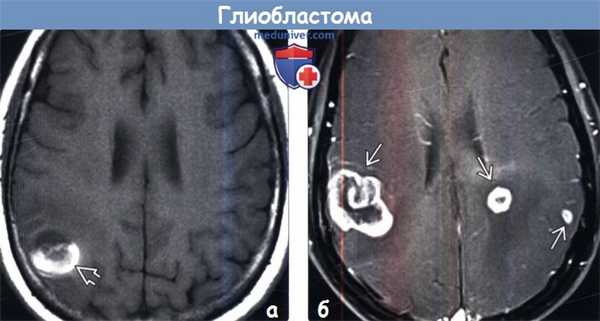

(а) МРТ, Т1-ВИ, аксиальный срез: у женщины 62 лет определяется объемное образование с геморрагическим компонентом (соответствующим областям укорочения Т1, что обусловлено наличием продуктов распада крови в подострой стадии). При биопсии была диагностирована МТБ. МТБ всегда нужно предполагать у пациентов старшего возраста с внутричерепным кровоизлиянием неясного генеза без артериальной гипертензии в анамнезе.

(б) МРТ, постконтрастное Т1-ВИ, аксиальный срез: у мужчины 72 лет визуализируются три отдельные зоны контрастирования, представляющие собой мультифокальную МГБ. Подобное синхронное возникновение МГБ встречается не более чем в 5% случаев.4. Радионуклидная диагностика: